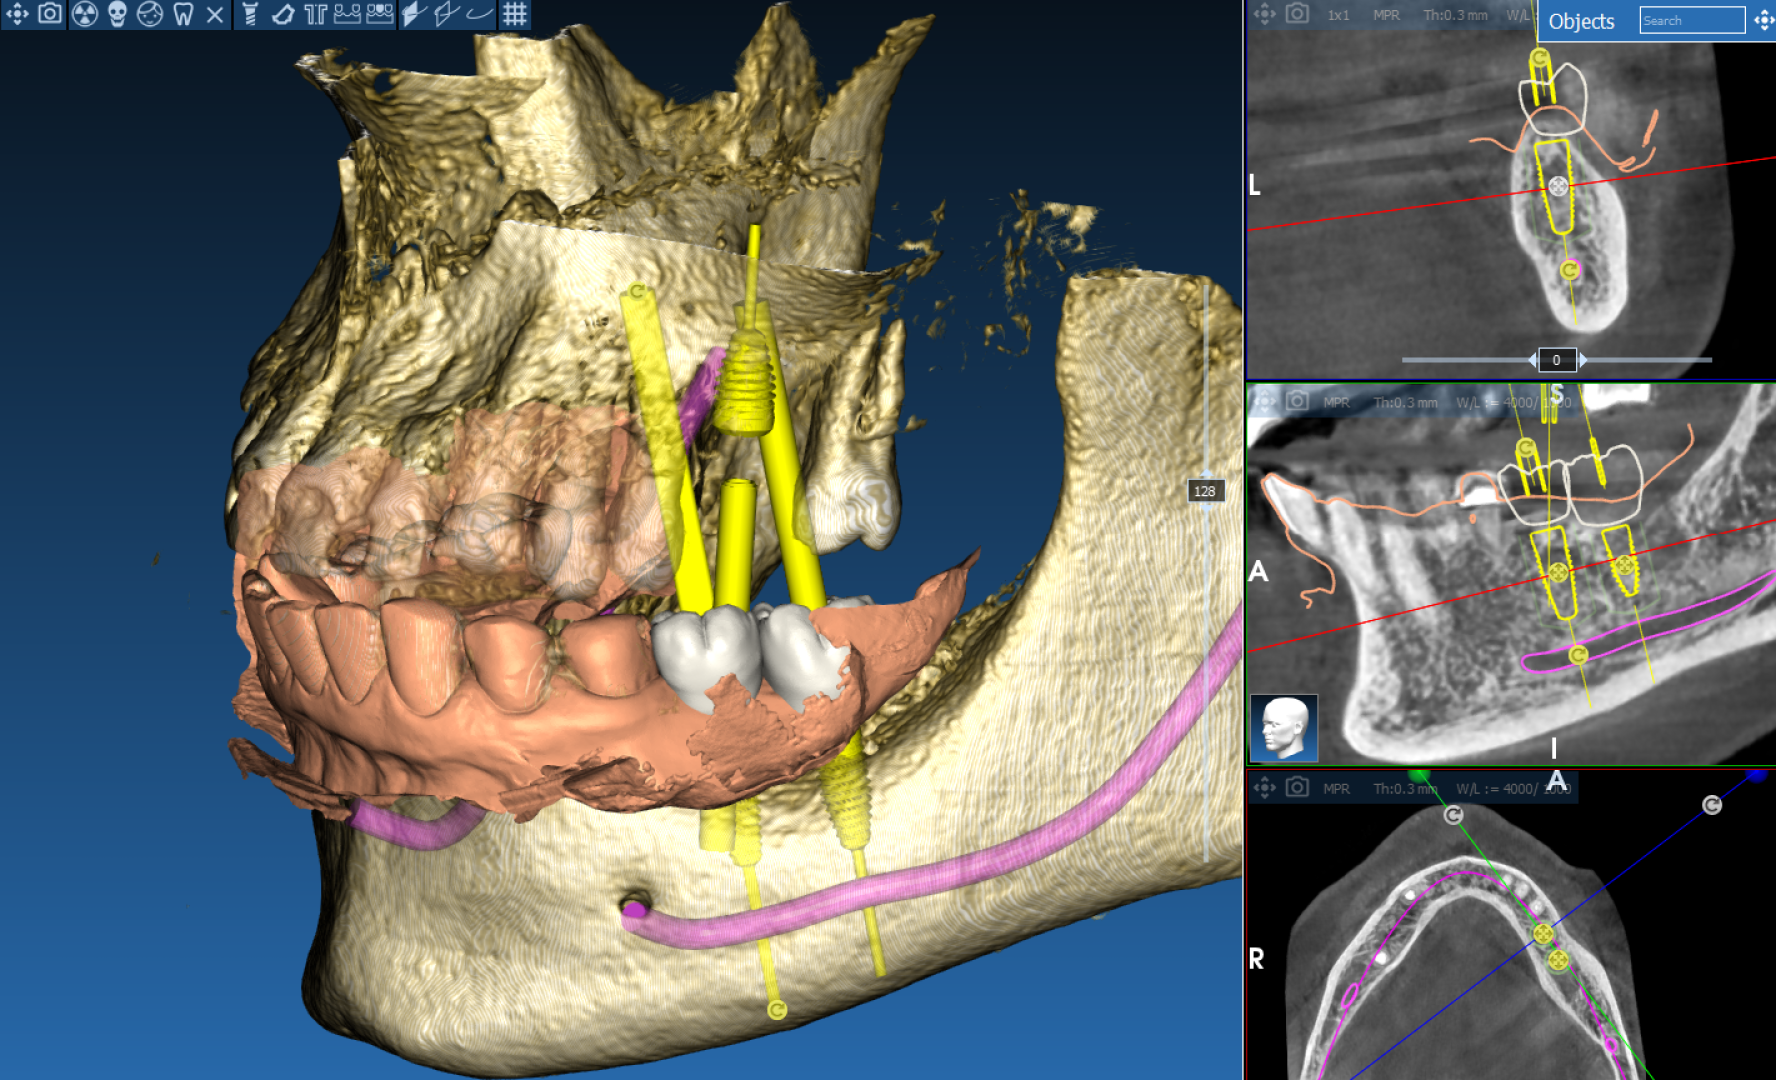

Хирургический 3D-шаблон для имплантации: планирование установки имплантов

Необходимость восстановления отсутствующих зубов с помощью имплантации. Требовалось максимально точное и безопасное позиционирование имплантов в костной ткани для долгосрочного прогноза и эстетики.